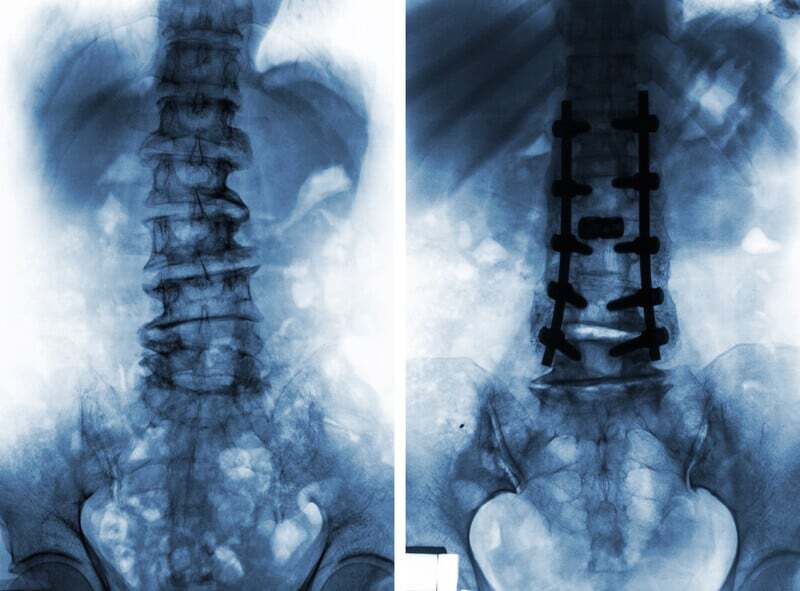

Many people email us about their hip and back pain. Some have been recommended to a hip replacement, some have been recommended to a spinal surgery. Some have been recommended to both surgeries and they are in the process of choosing between one or the other and exploring options to help them avoid one or the other surgery, even both.

Back surgery? Hip Surgery? Do you need either? Both? Neither?

The problem of hip-spine complex pain is that it is indeed a complex problem of hip and spine pain. As we will see in the research below, problems of the hip / spine may lead some people to get a back surgery for a hip problem and a hip surgery for a back problem. Doctors have noted that the symptoms of hip arthritis pain and spinal stenosis leg pain can be very similar, with only subtle differences in both history and clinical physical examinations. Spinal stenosis is classically diagnosed in patients with leg pain that occurs during standing or walking and is relieved when the individual sits down.

Research: The question of which to have surgery on first, the hip or the spine, is much more complex and risky than thought

The option to have lumbar spinal surgery and hip replacement at the same time is clearly one that is not recommended for obvious reasons. So a decision has to be made. Spinal surgery or hip replacement surgery? One has to come first and one has to wait.

Hip or spine surgery first? Research says there is confusion and controversy even among the most experienced surgeons

Because you cannot do a spinal surgery and a hip replacement at the same time the patient and their surgeons need to pick the one that helps the most. If you went to your hip surgeon, he/she may recommend the hip first, if you went to your spinal surgeon he/she may recommend spinal surgery first. So you have 2 different “first surgery,” recommendations. Sometimes, there is agreement, sometimes there is conflicting opinions.